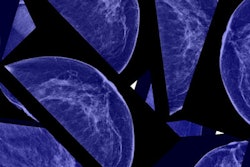

A team led by Marco Huesch, PhD, of Pennsylvania State University, investigated the impact on the use of screening mammography of actor Angelina Jolie's 2013 announcement that she had undergone a prophylactic double mastectomy. The researchers compared weekly utilization in the two years before and after the announcement, including 48,110 consecutive screening mammograms conducted between May 2011 and May 2015.

Huesch and colleagues found no upsurge in screening mammography around May 2013, and, in fact, they noticed a flattening of utilization in the middle of 2014.